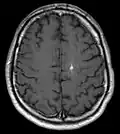

Diagnosis is generally made by magnetic resonance imaging (MRI), particularly using a specific imaging technique known as a gradient-echo sequence MRI, which can unmask small or punctate lesions that may otherwise remain undetected. These lesions are also more conspicuous on FLAIR imaging compared to standard T2 weighing. FLAIR imaging is different from gradient sequences. Rather, it is similar to T2 weighing but suppresses free-flowing fluid signal. Sometimes quiescent CCMs can be revealed as incidental findings during MRI exams ordered for other reasons. Many cavernous hemangiomas are detected "accidentally" during MRIs searching for other pathologies. These "incidentalomas" are generally asymptomatic. In the case of hemorrhage, however, a CT scan is more efficient at showing new blood than an MRI, and when brain hemorrhage is suspected, a CT scan may be ordered first, followed by an MRI to confirm the type of lesion that has bled.[19] Sometimes the lesion appearance imaged by MRI remains inconclusive. Consequently, neurosurgeons will order a cerebral angiogram or magnetic resonance angiogram. Since CCMs are low flow lesions (they are hooked into the venous side of the circulatory system), they will be angiographically occult (invisible). If a lesion is discernible via angiogram in the same location as in the MRI, then an arteriovenous malformation (AVM) becomes the primary concern.